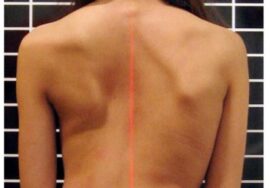

اعوجاج العمود الفقري عند الأطفال والمراهقين هو انحناء جانبي في العمود الفقري يظهر غالبًا خلال فترة النمو السريع، عادة بين عمر 10 و16 عامًا. الانحناءات الصغيرة قد تكون غير واضحة في البداية، لكن مع الوقت يمكن أن تزداد سوءًا إذا لم يتم التعامل معها.

قد يلاحظ الأهل بعض العلامات البسيطة، مثل:

ميلان الكتفين أو عدم تساويهما

بروز أحد الضلوع أكثر من الآخر

ميلان الجسم إلى أحد الجانبين

اختلاف مستوى الخصر أو الظهر

الفحص السريري المنتظم: لملاحظة الميلان أو تغير مستوى الكتفين والخصر.